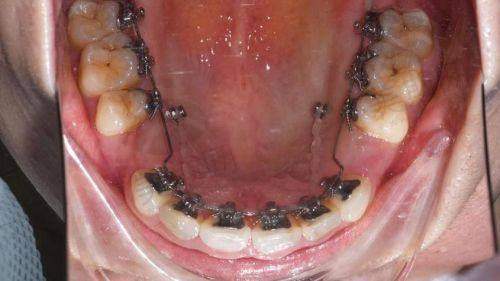

2. 技术水平:医院在牙齿矫正技术方面表现出色。涵盖了传统金属托槽矫正,包括普通金属托槽和金属自锁托槽;陶瓷半隐形矫正,有普通陶瓷托槽和陶瓷自锁托槽;隐形矫正,有国产的时代天使和进口的隐适美;还有舌侧矫正、儿童早期干预矫正、正畸正颌联合治疗等多种技术。能针对不同牙齿畸形情况提供合适的矫正方案。在种植等方面,医院使用高端材料,与瑞士Straumman亲水种植、德国强直等优质技术提供商形成战略合作伙伴,有相关技术支持。

舌侧矫正:价格40000元起,它将矫正器安装在牙齿内侧,从外观上几乎看不到矫正器,满足了患者对美观和矫正成效的双重需求。